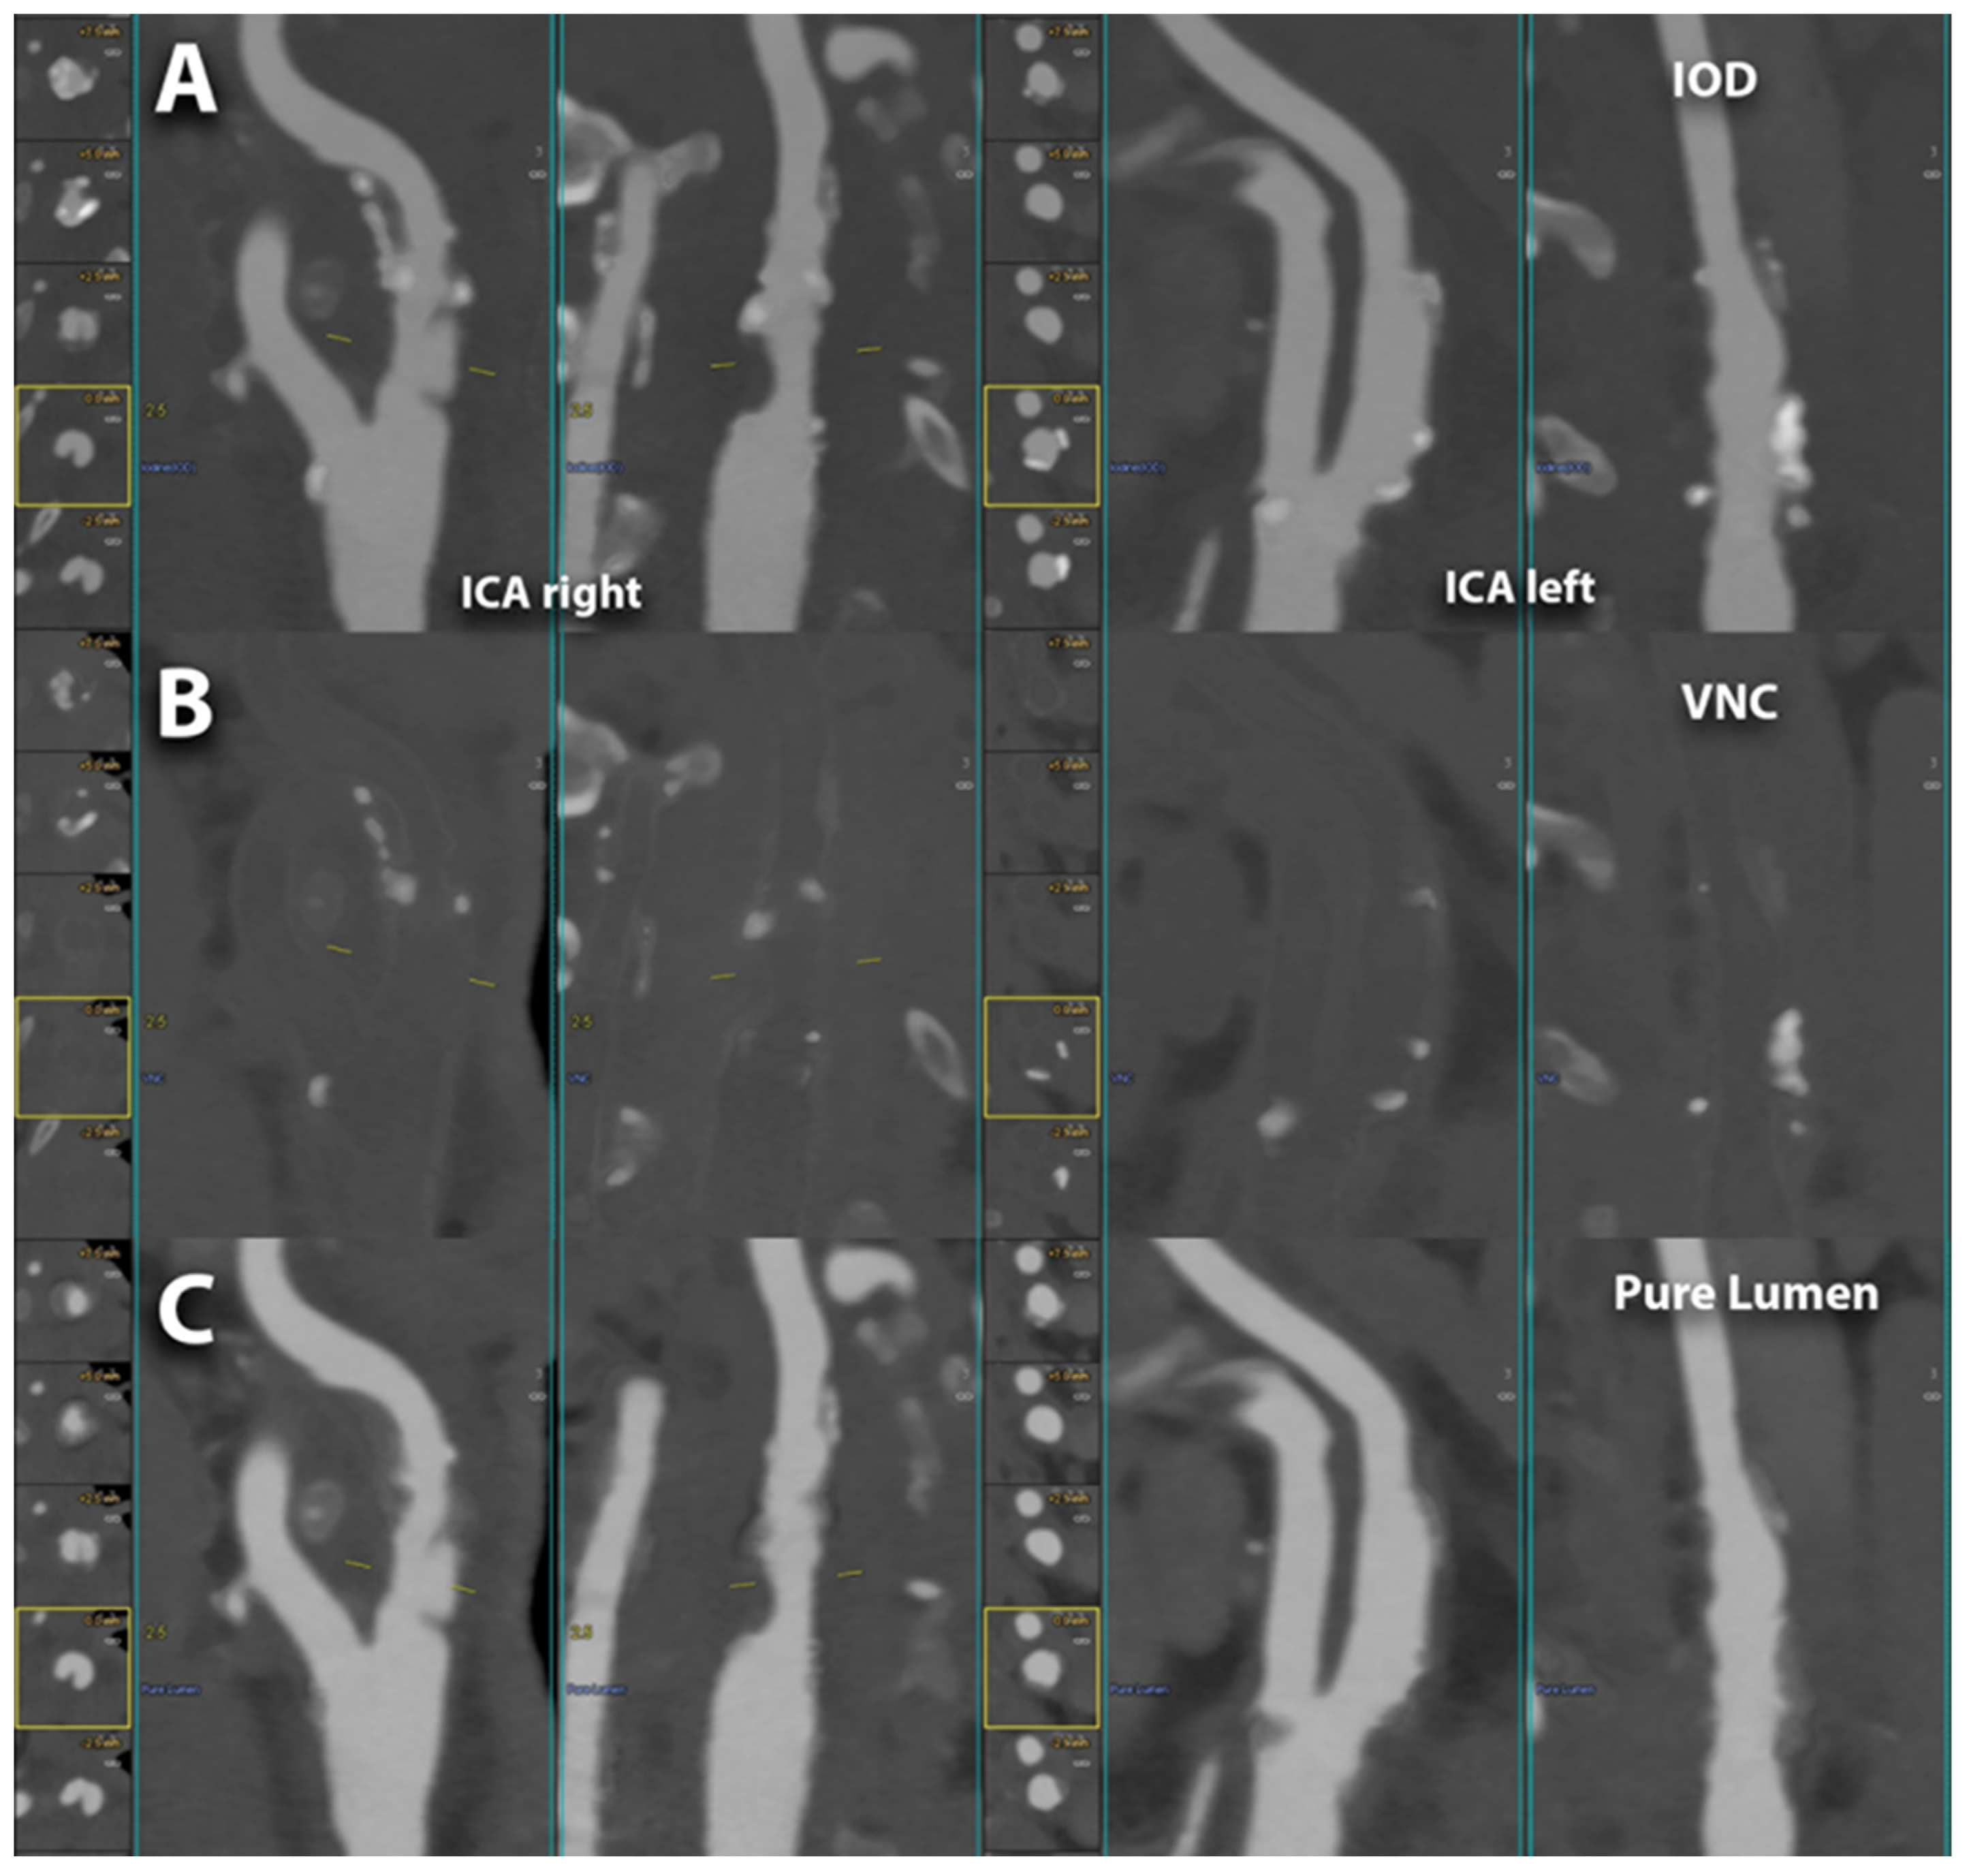

6.1. Carotid Lumen Evaluation